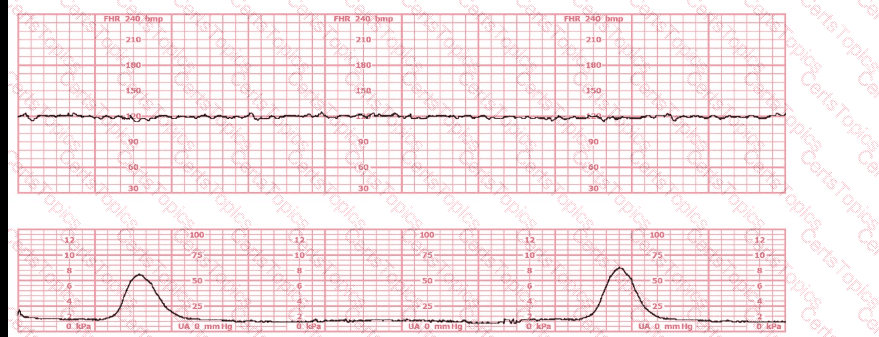

The tracing shown is a:

This tracing demonstrates:

This tracing would be categorized as a

This tracing reflects: